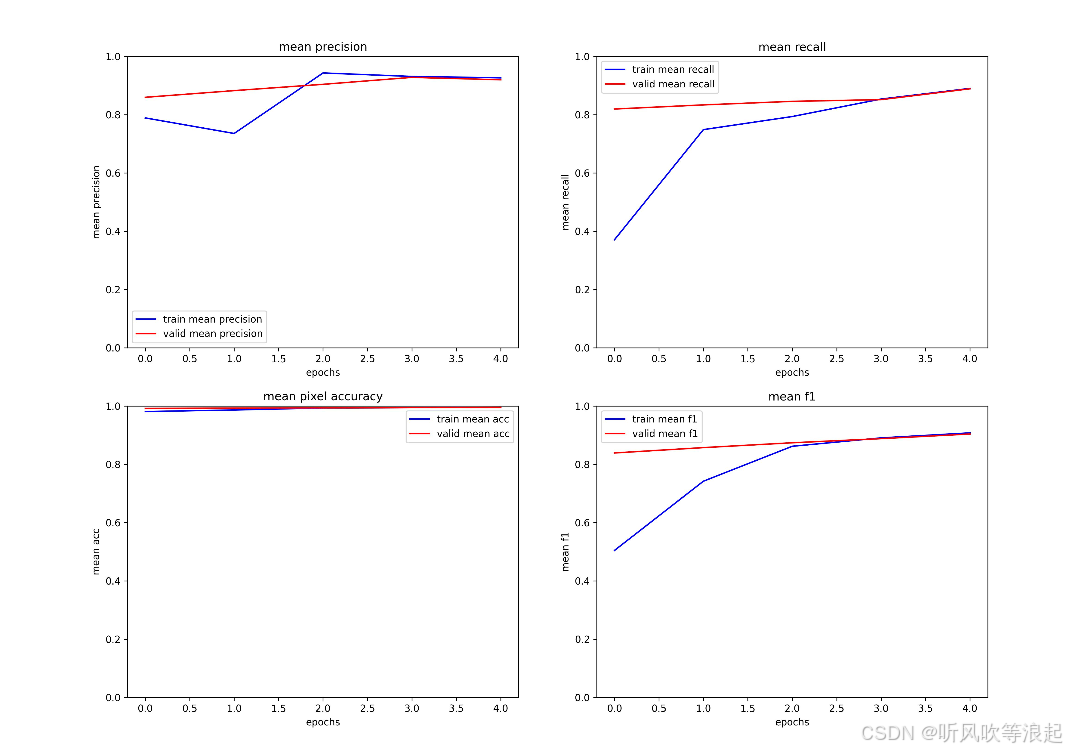

return lr, loss.item(), miou, mdice, confmat评估指标包括:

- 像素准确率(Pixel Accuracy)

- 平均交并比(mIoU)

- Dice系数

- 精确率(Precision)

- 召回率(Recall)

- F1分数

这里仅仅训练了5个epoch用于测试代码的可行性,指标不做参考

因为unet的结果很好,这里只展示unet,而非deeplabv3